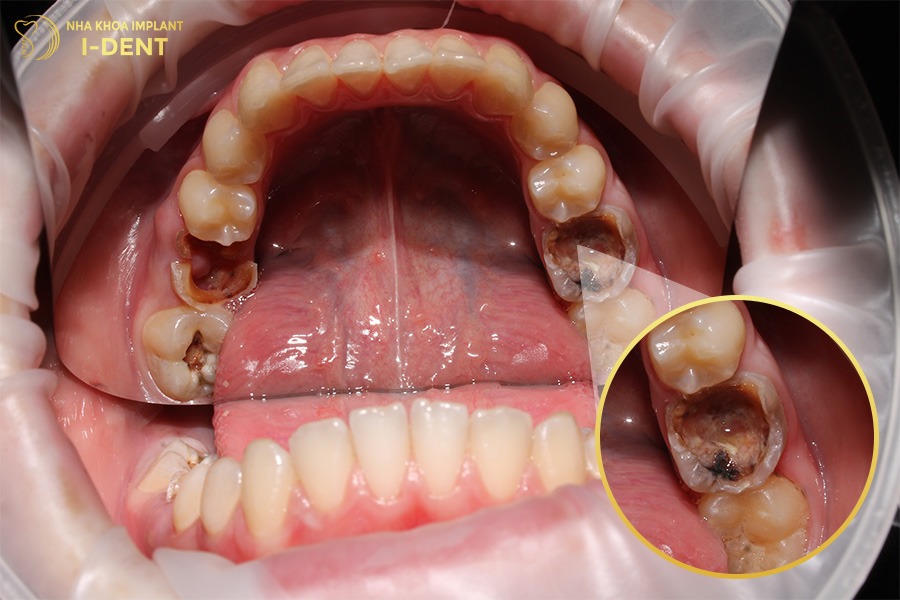

- Sâu răng, viêm nướu: Răng số 6 bị sâu nếu không được điều trị kịp thời sẽ làm ảnh hưởng các lớp cấu trúc răng dẫn đến không giữ được răng. Tương tự, viêm nướu thời gian dài dễ dẫn đến viêm nha chu gây mất răng số 6.

Sâu răng có thể làm mất răng số 6